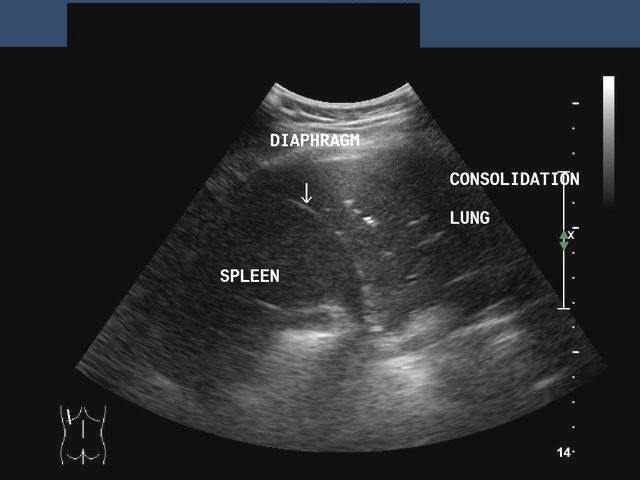

Pulmonary consolidation

Sonography of the left lung reveals loss of normal aeration of the lung parenchyma with echogencity and texture similar to that of the spleen below. The echogenic left dome of diaphragm is seen separating the lower lobe of the lung from the spleen. The normal aerated lung surface would reflect all the sound waves producing a strong shadow. These ultrasound images suggest consolidation of the lung. Image courtesy of Dr. Gunjan Puri, Surat, India. Image taken using a Toshiba Xario, ultrasound and color doppler machine.